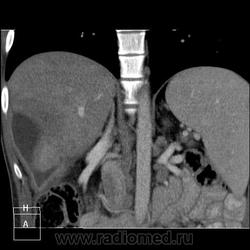

КТ (часть кадров выложу позже ). Цель направления на КТ - образование правой доли печени, исключить образование тела п.ж.

). Цель направления на КТ - образование правой доли печени, исключить образование тела п.ж.

В данном случае ранняя артериальная получилась с брачком - контрастировалась нижняя полая (25 сек задержка, триггера нет), панкреатическая 45 сек (стандарт), портальная 70 сек. Отсроченная в печени делается на подозрение на холангиокарциному и гемангиому. Тут почки и не интересовали.

Гемангиома, являясь сосудистой опухолью, будет такого же цвета, как и сосуды, во все фазы. Это - кистовидное образование, стенки относительно равномерной толщины, копящие контраст тонкой полоской. Содержимое образования жидкостной плотности и контраст не копит.

Гепатоспленогмегалия. Начальная портальная гипертензия, холедох не расширен. В воротах печени бугристая масса.... чего? Кальцинаты поджелудочной железы, мелкий камушек в желчном. Вопрос в том, что за кистовидное образование, что за полоса-серп вокруг желчного пузыря, что в воротах печени. Опухоли п.ж. я не нашла.

Данному пациенту в заключении я выставила подпеченочный абсцесс, гепатоспленомегалию, портальную гипертензию, конгломерат лимфоузлов ворот печени, лимфаденопатию желудочной группы л/у, хр.калькулезный панкреатит, ЖКБ с перихолециститом.

В воротах, похоже л/у, а жидкостное абсцесс печени.

Абсцесс печени.